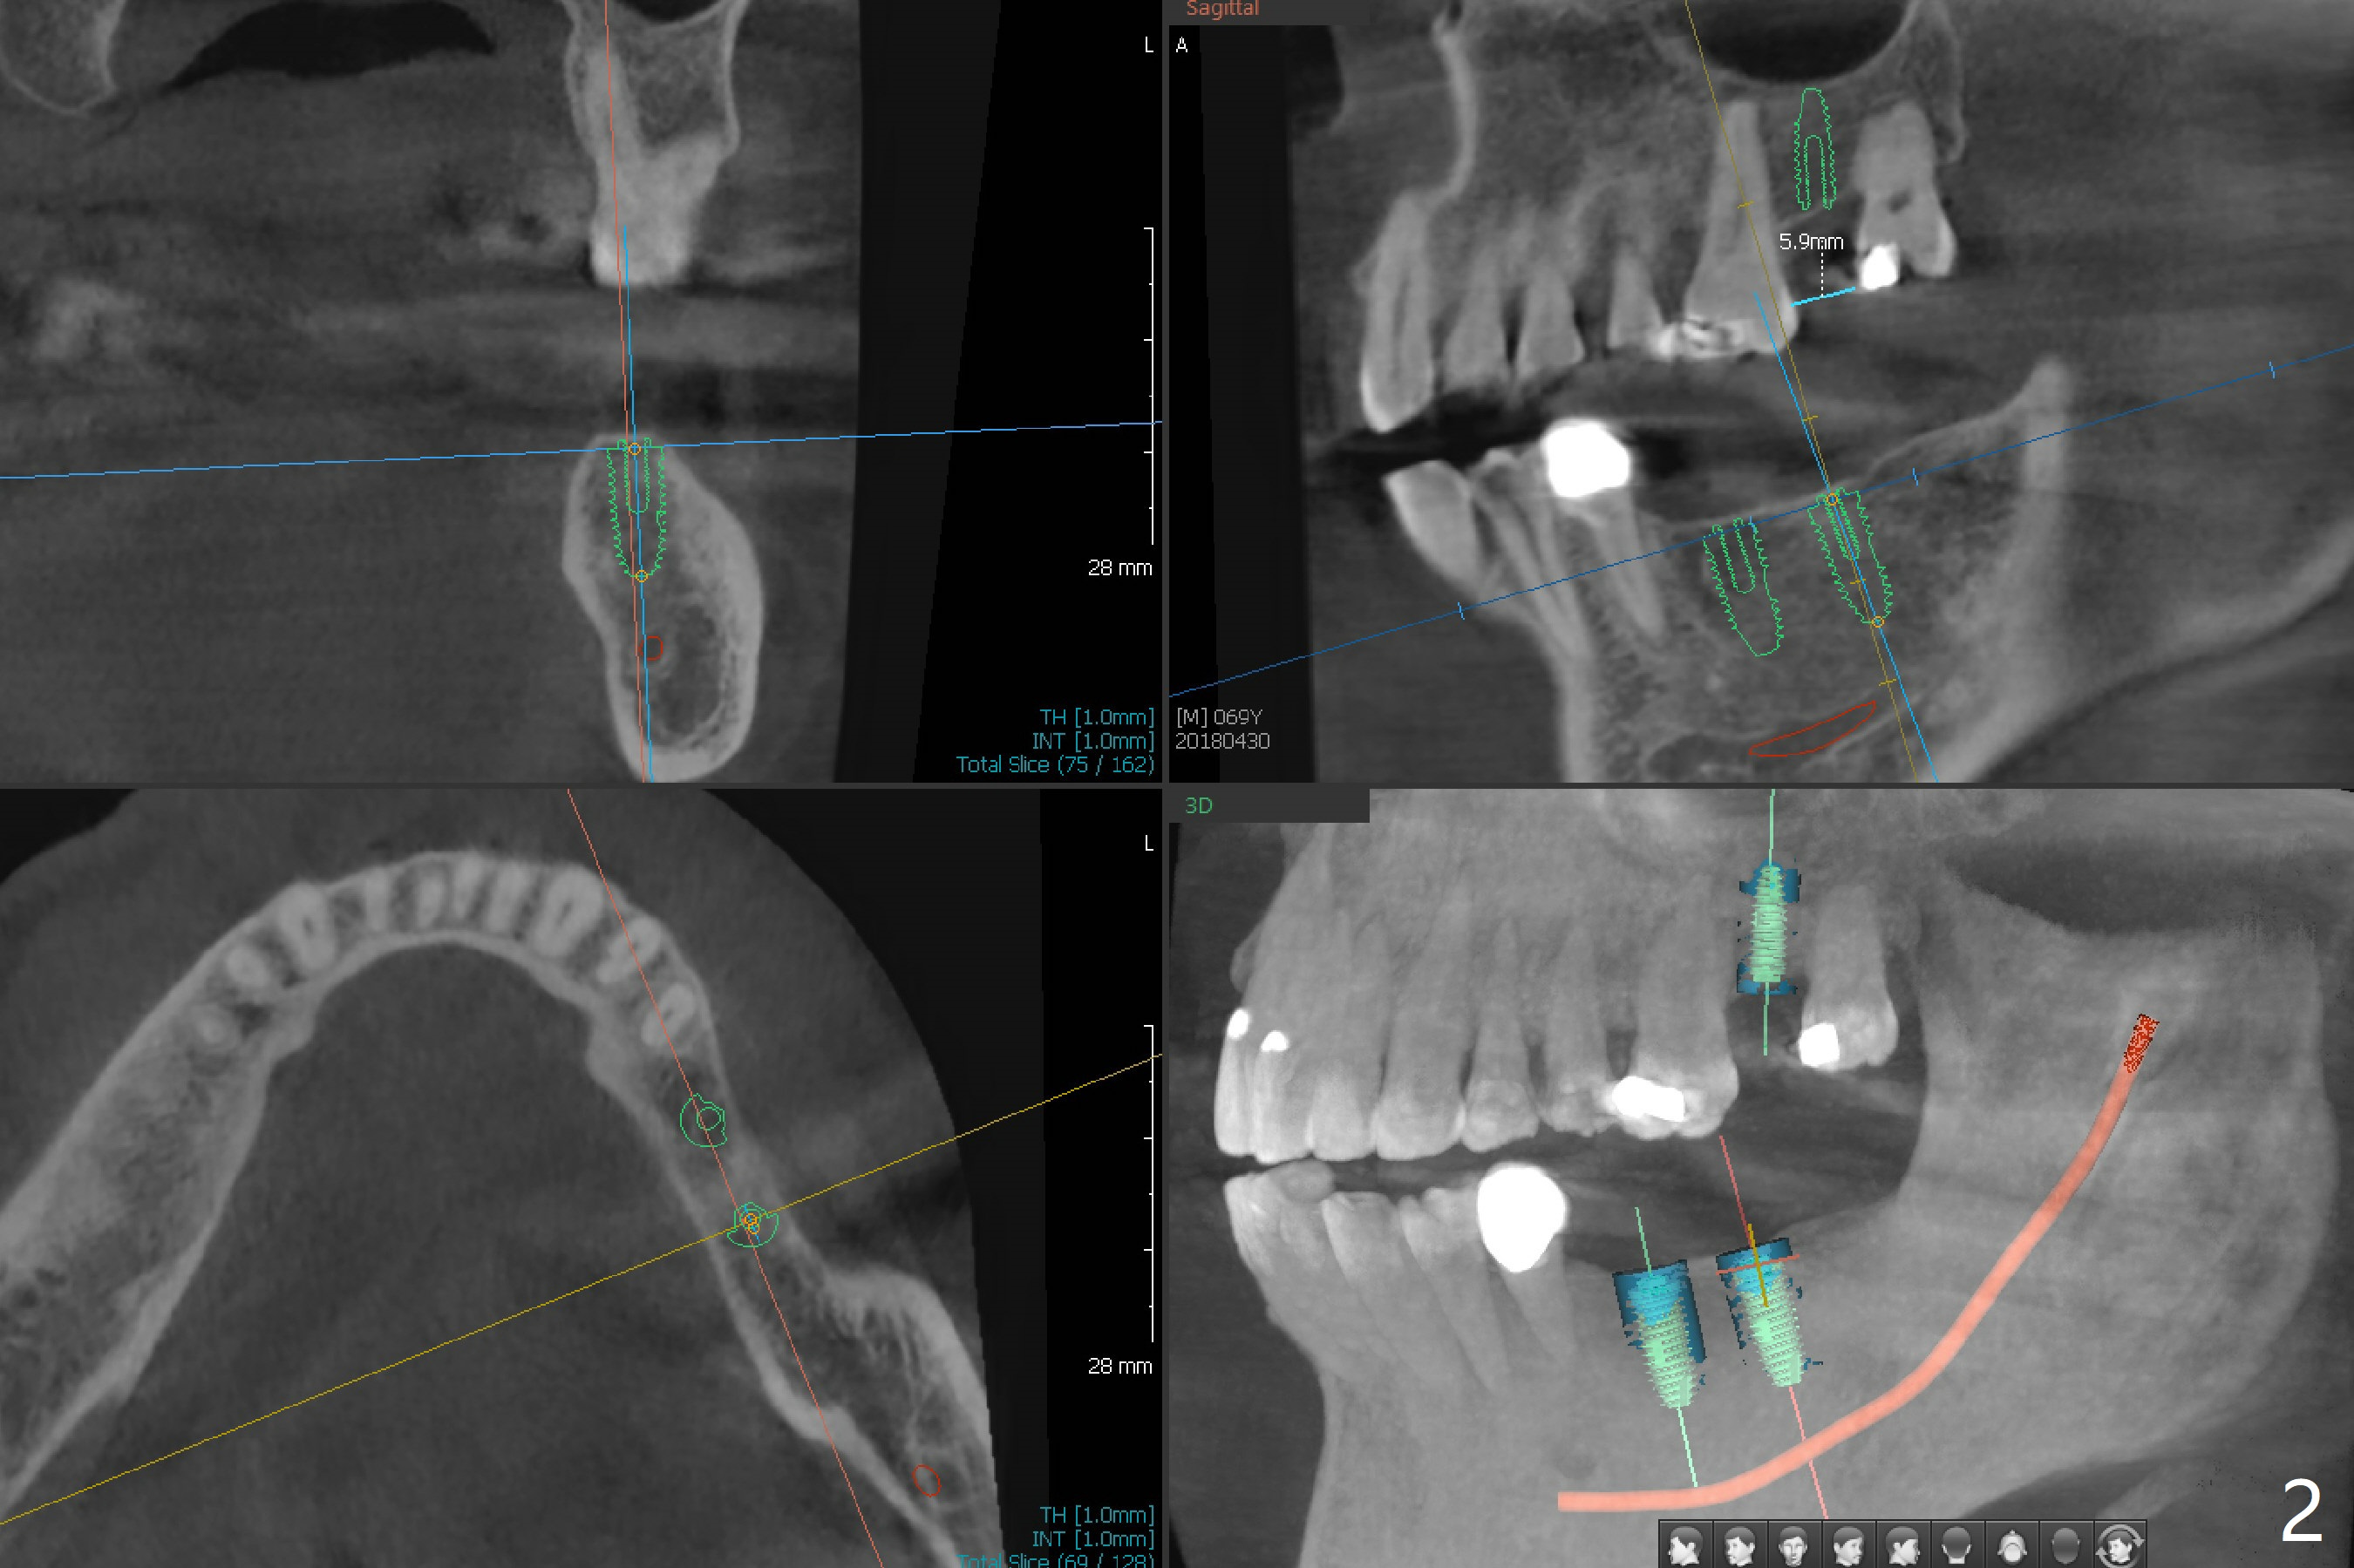

A 69-year-old man has 3 missing teeth: #15, 18 and 19 (Fig.1,2). He wants an implant at #19 first. A guide will be fabricated for #18 and 19 first. If he wants to have an implant at #18 later, the crown/abutment at #19 will be removed and an implant anchor will be used at #19 for #18 guided surgery. The upper model will remain or be resent to the guide lab for #15 guide if needed.